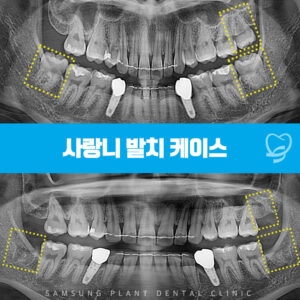

신정네거리역치과 신속하고 깔끔하게 사랑니발치를!

신정네거리역치과 신속하고 깔끔하게 사랑니발치를! . 삼성플란트치과에서는 디지털 장비를 사용해 사랑니의 위치와 방향, 신경관의 위치, 주변 치아와의 관계 등을 정밀하게 평가하여 발치 계획을 수립하고 있습니다. 또한 꼼꼼한 치료계획을 바탕으로, 일대일…